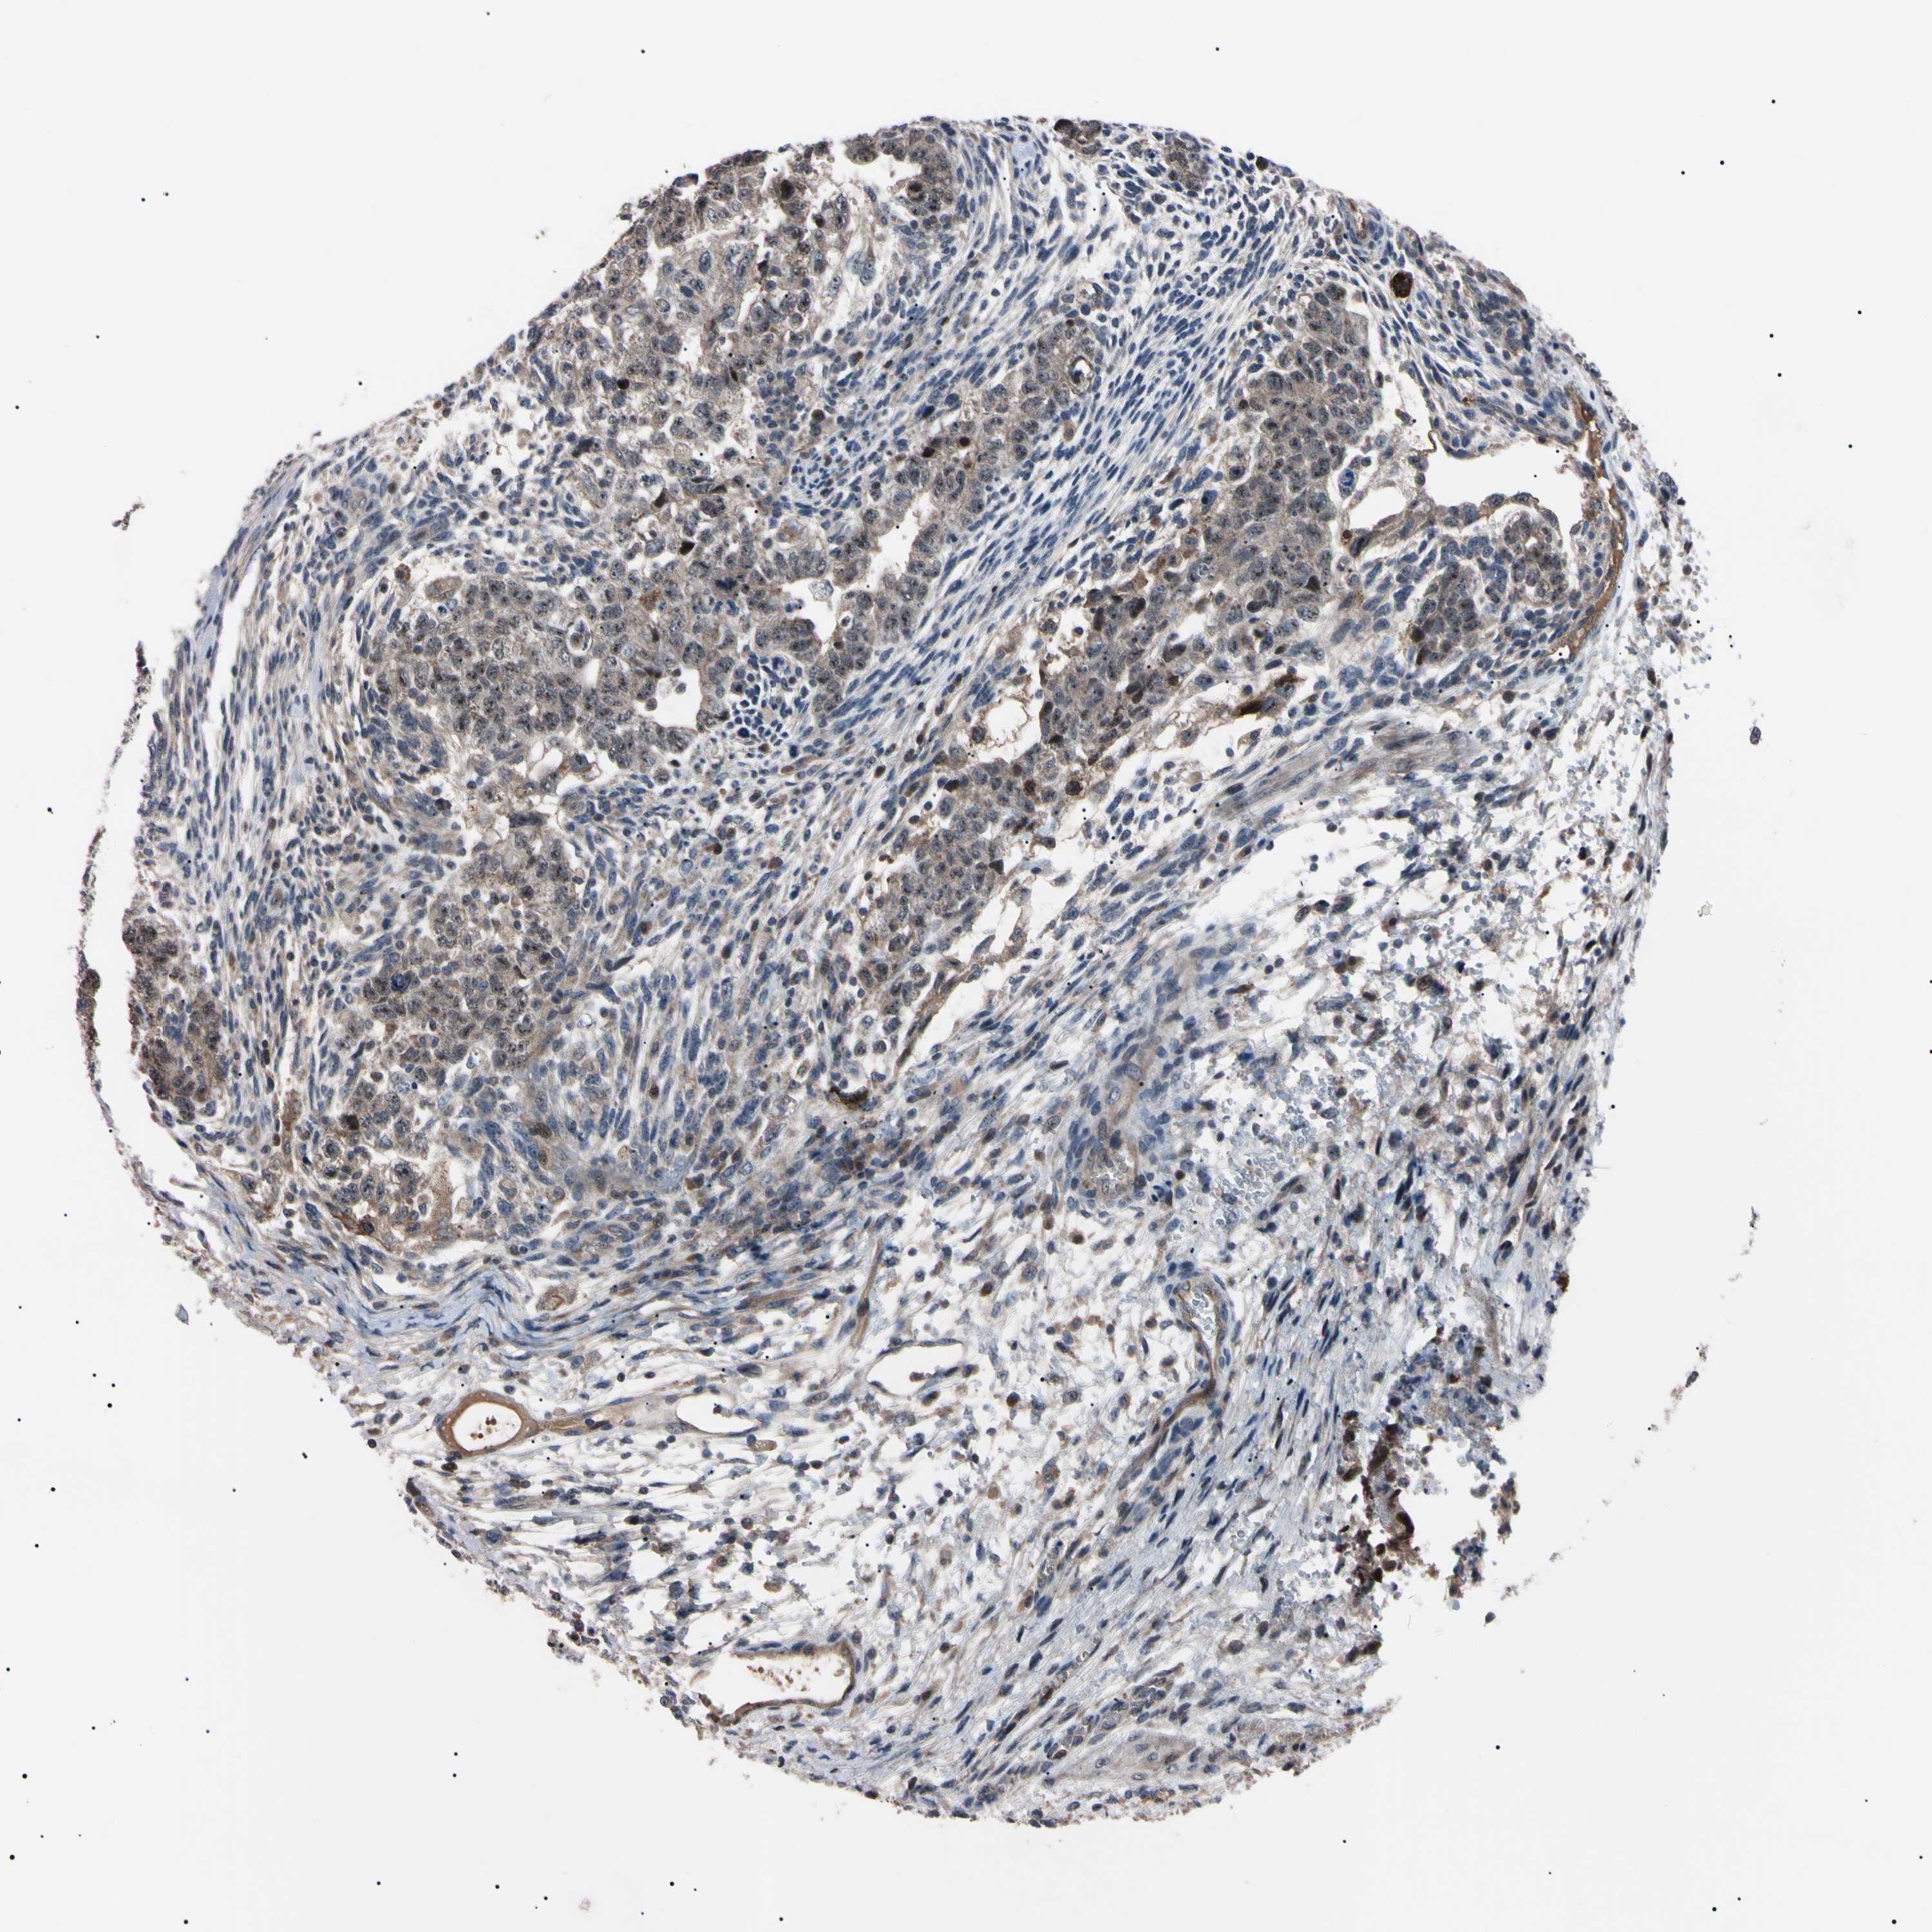

TESTIS CANCER - Protein expressioni

A mouse-over function shows sample information and annotation data. Click on an image to view it in a full screen mode. Samples can be filtered based on level of antibody staining by selecting one or several of the following categories: high, medium, low and not detected. The assay and annotation is described here.

Note that samples used for immunohistochemistry by the Human Protein Atlas do not correspond to samples in the TCGA dataset.

Antibody stainingi

Antibody staining in the annotated cell types in the current human tissue is reported as not detected, low, medium, or high, based on conventional immunohistochemistry profiling in selected tissues. This score is based on the combination of the staining intensity and fraction of stained cells.

Each image is clickable and will lead to virtual microscopy that enables deeper exploration of all samples and also displays staining intensity scores, fraction scores and subcellular localization as well as patient and tissue information for each sample.

Antibody HPA008052

Antibody CAB010277

Carcinoma, Embryonal, NOS

Seminoma, NOS